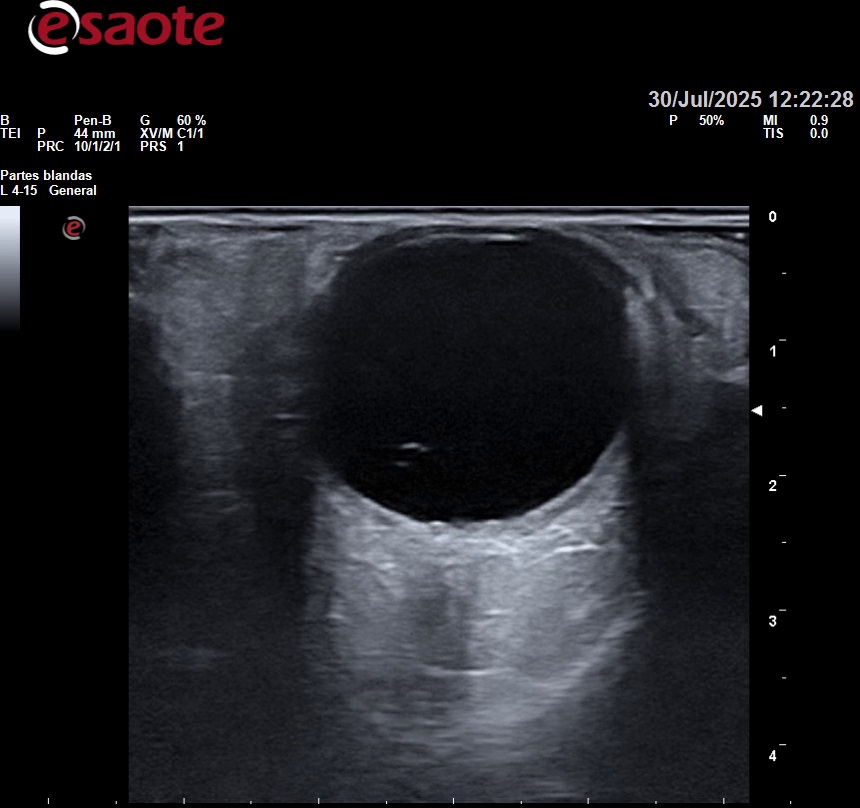

Se realiza una Ecografía ocular.

Hallazgos ecográficos

Cornea, cámara anterior, iris y cristalino sin alteraciones de interés.

Se realiza barrido del globo ocular en corte longitudinal, transversal y con movimientos oculares. Observándose un punto y líneas hiperecogénicas flotando en vítreo desplazándose con movimientos oculares.

Exploración de nervio óptico sin presentar alteración estructural y con captación de doppler normal.

Presenta microdesopsias previas, aparición de fotopsias sin alteración de la visión, ni clínica neurológica. Exploración anodina y hallazgo ecográfico de imágenes lineales hiperecogénicas flotando en globo ocular.

Se sospecha de Desprendimiento de Vítreo Posterior.